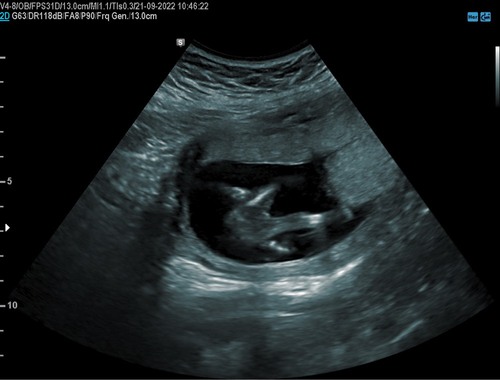

Ik heb vorige week een echo gehad van iemand die nog aan het oefenen is met echo’s en die zei een meisje. Ik heb morgen nog een echo in het echo centrum voor geslachtsbepaling dus dan heb ik bevestiging 😂

Vandaag bevestiging gekregen! Het is echt een meid!

Het is echt een meisje!